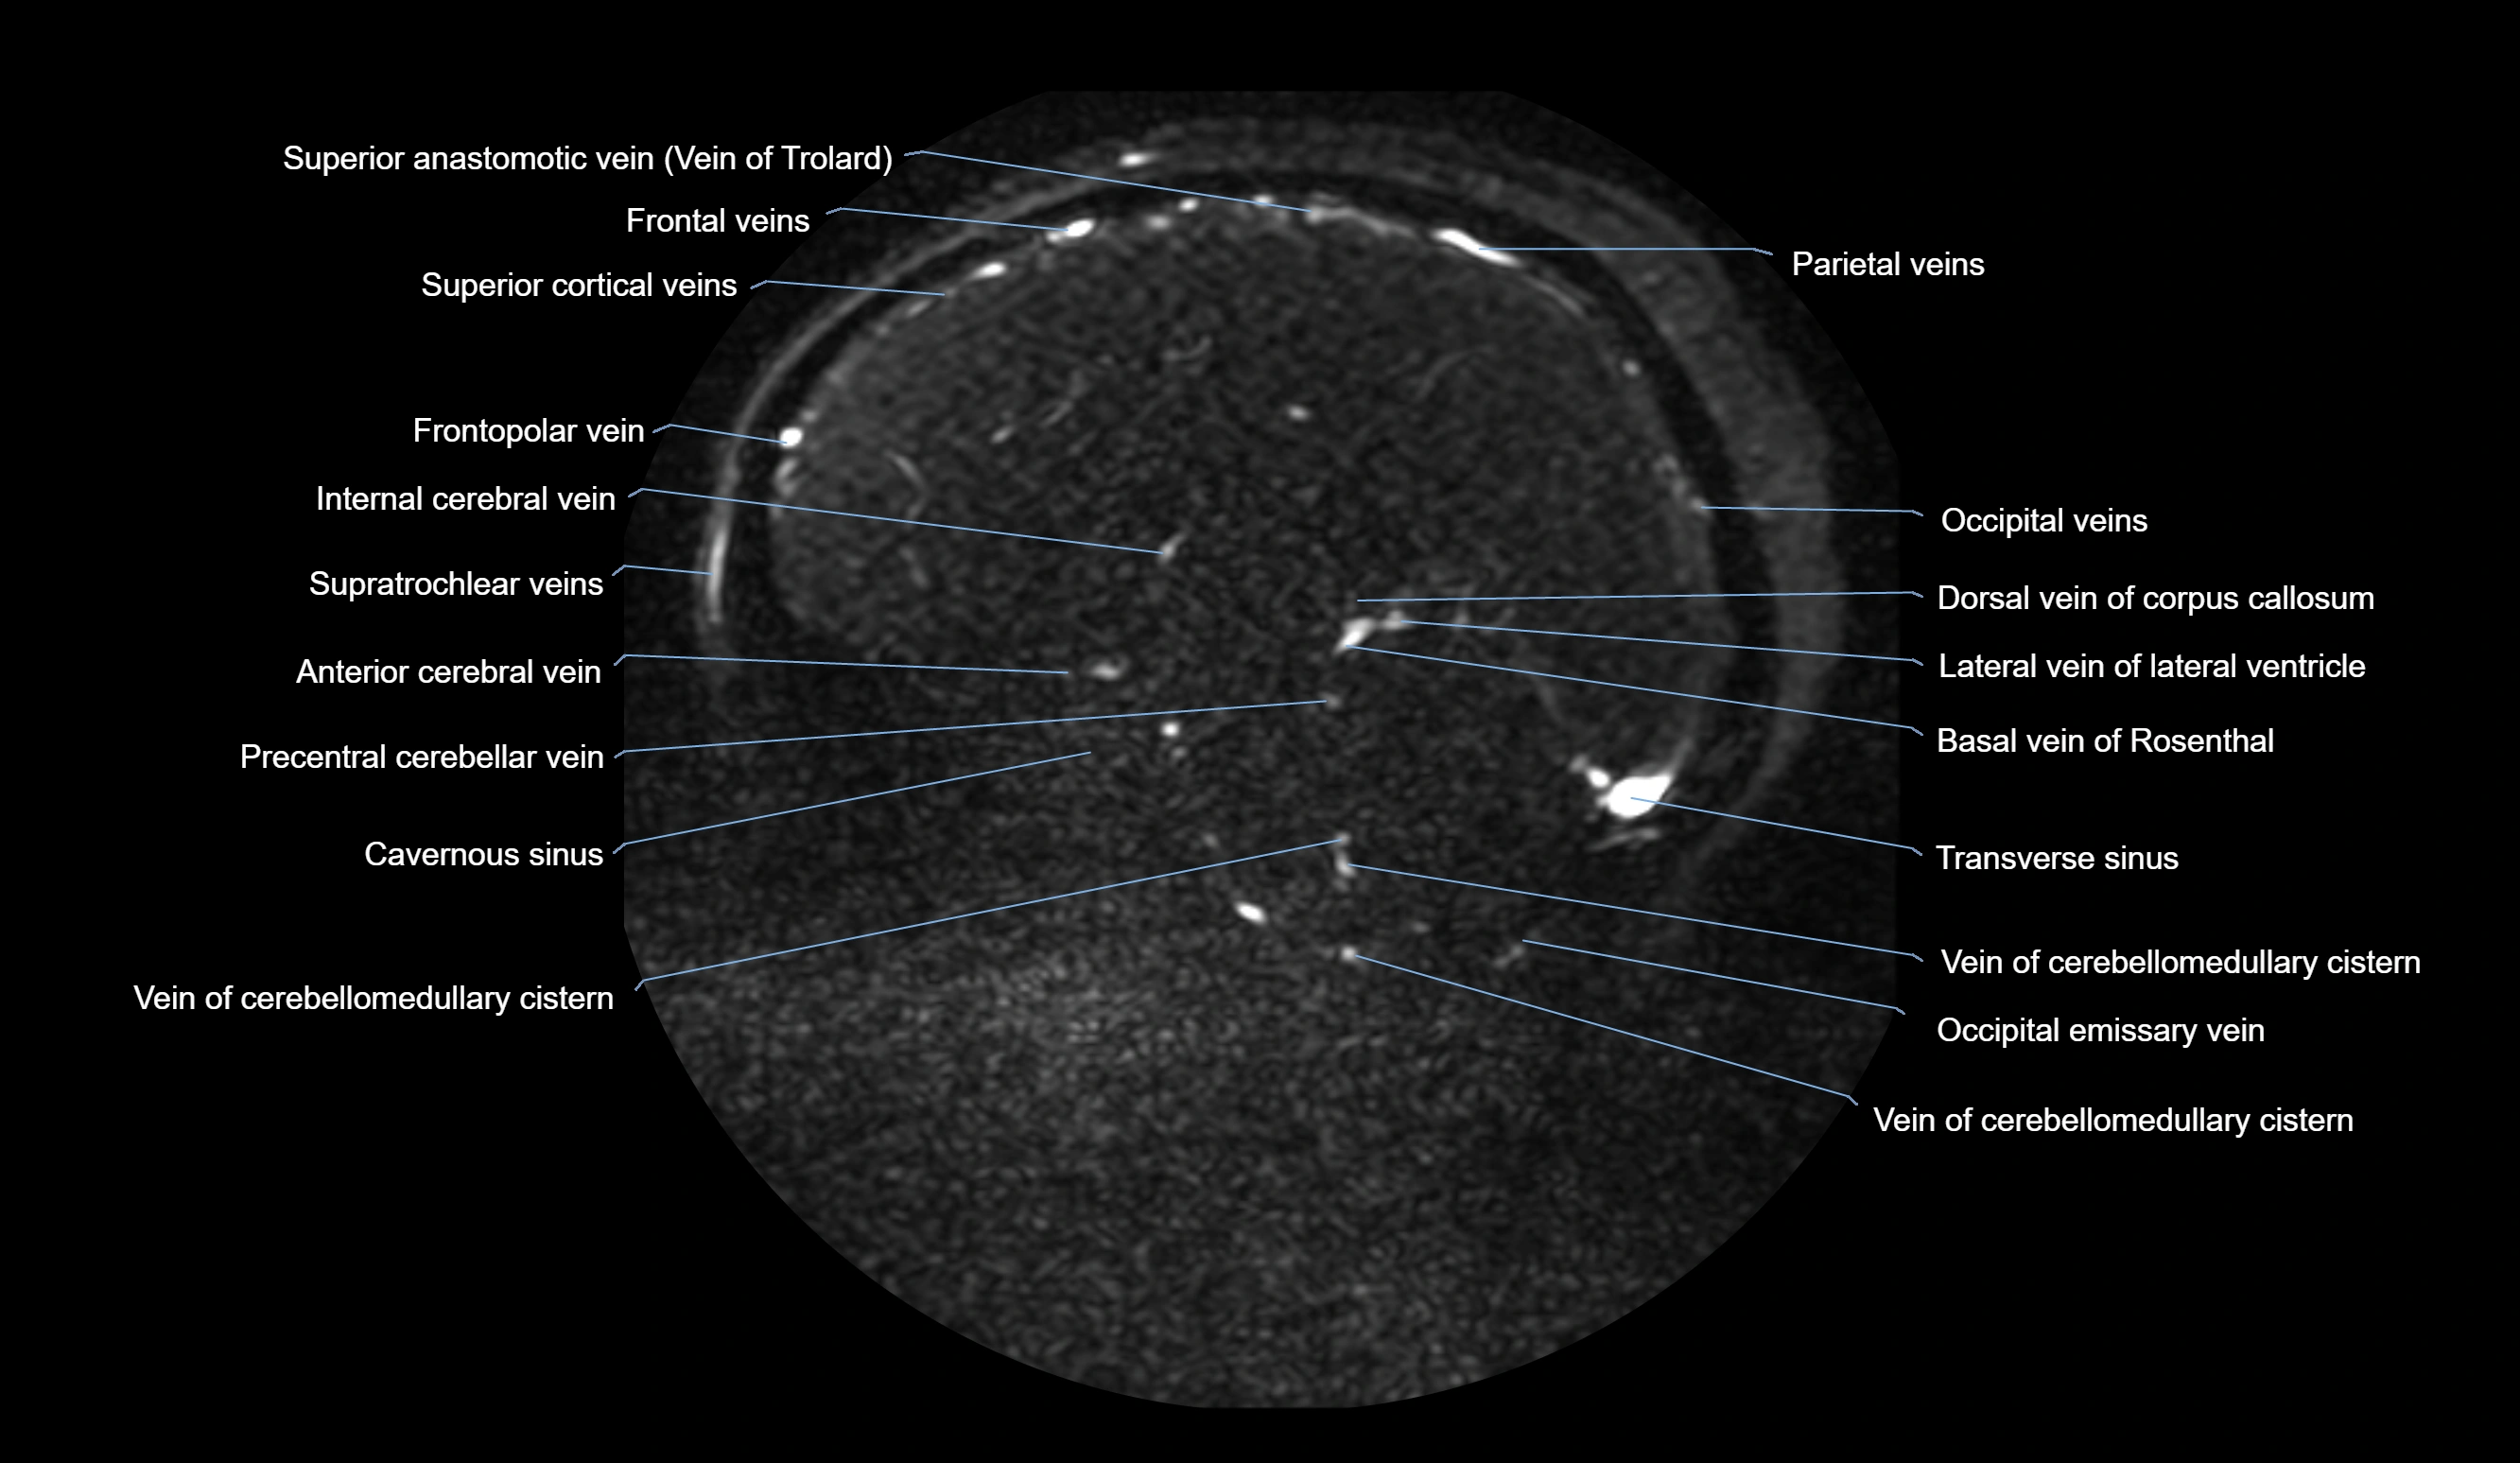

CT Venography (CTV):

• Clearly visualizes the angular vein as a contrast-filled venous channel

• Demonstrates its communication with the facial vein, superior ophthalmic vein, and cavernous sinus

• Essential for detecting facial vein thrombosis, orbital venous involvement, and cavernous sinus pathology